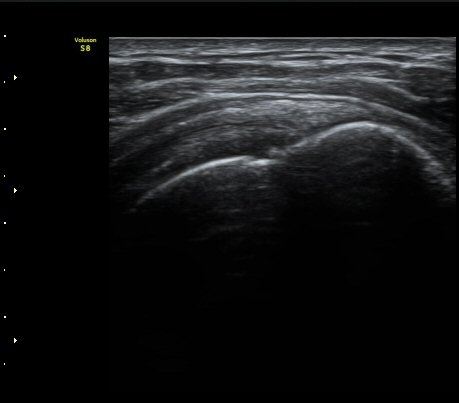

±Ø»ó°Ç Á¾´Ü¸é°Ë»ç¿¡¼­ ´ë°áÀý°ú »ó¿Ï°ñµÎ ÀÌÇàºÎÀ§¿¡ ÇÇÁú°ñ ¿¬¼Ó¼º ¼Ò½ÇÀ» º¸ÀÓ(±×¸² 3, 4, 5)

±Ø»ó°Ç ¿øÀ§ºÎ Ⱦ´Ü¸é°Ë»ç¿¡¼­ ´ë°áÀý°ú »ó¿Ï°ñµÎ ÀÌÇàºÎÀ§¿¡ ÇÇÁú°ñ ¿¬¼Ó¼º ¼Ò½ÇÀ» º¸ÀÓ(±×¸² 7).